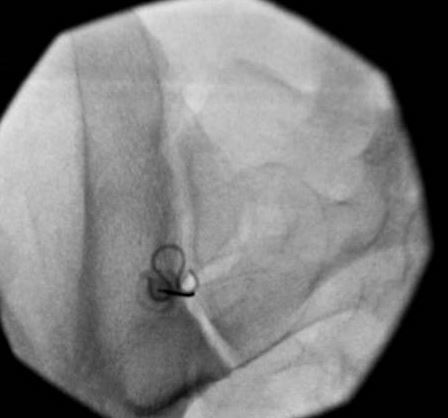

I don't ever take laterals unless things really aren't adding up or I've got a medical student and I'm trying to be academic. Here are a few below.

Typically start 5-10 degrees feet tilt, 10-15 degrees contra-oblique and then adjust the oblique until I find what seems right for the joint.

Screenshot 2023-01-19 185009.jpg

Screenshot 2023-01-19 185100.jpg